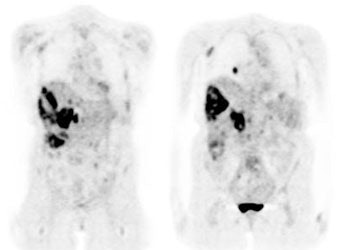

Diffuse splenic involvement: The patient shown below has non-Hodgkins lymphoma. The FDG PET exam demonstrated multiple sites of disease including diffuse involvement of the spleen, focal liver involvement, and persistent sites of adenopathy in the chest and abdomen. Case courtesy of Mercy Medical Center Alliance Imaging, Dr. Steve Allen. |

|

FDG PET imaging is more accurate than CT for the detection of lymphomatous involvement of the spleen [5,27]. On FDG PET imaging, diffuse or focal splenic uptake of greater intensity than the liver is felt to represent tumor involvement [27]. Infiltrative lymphomatous involvement of the spleen can be detected with a 67% increased frequency when compared with CT imaging [5]. Hepatic tumor involvement is characterized by focal or diffuse increased tracer accumulation [5].